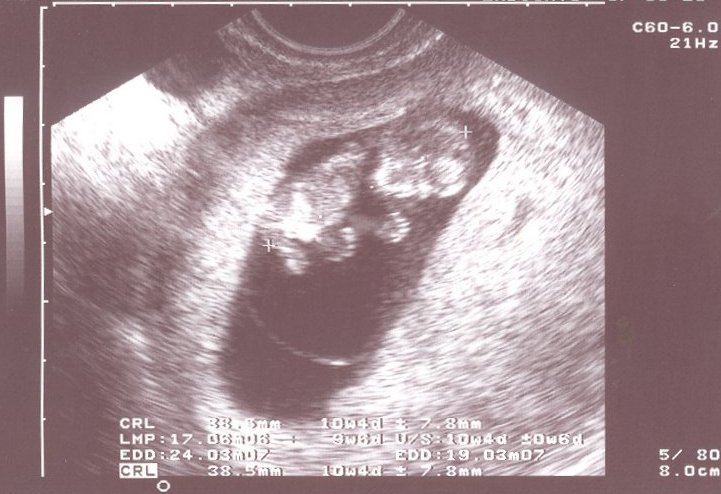

Maurice geb. am 17.05.2004 um 18.26 Uhr - 3770 gr.,55 cm groß und 38,5 cm Kopfumfang

Angelina geb. am 15.03.2007 um 7.30 Uhr - 3250 gr.,50 cm groß und 33 cm Kopfumfang